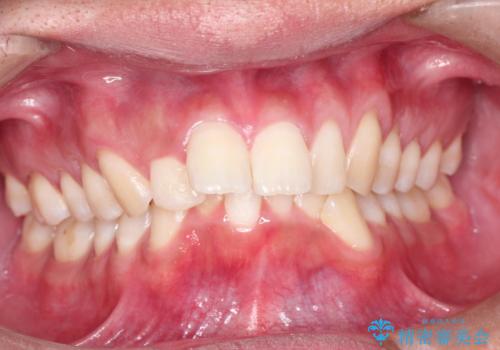

インビザラインによる出っ歯の矯正

- 出っ歯と下の歯のガタガタを主訴に来院されました。

上の奥歯を後方に移動させて、スペースを作り前歯を内側に引っ込める計画としました。

インビザラインによるマウスピース矯正で治療をすることとしました。

インビザラインをしっかり使用していただいたので、スムーズに治療をおえることができました。